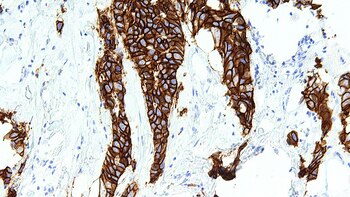

Entre el 15 y el 20 por ciento de las personas con cáncer de mama presentan niveles más elevados de una proteína llamada HER2. Por eso reciben el nombre de cánceres de mama “HER2-positivos”. Durante las últimas décadas, se desarrollaron terapias dirigidas que pueden ser indicadas para estos pacientes. Sin embargo, algunos registran resistencia al cabo de un año.

Ahora, un equipo de investigadores de España, Estados Unidos y China consiguieron identificar un conjunto de genes en ratones, que podría abrir la puerta a nuevos tratamientos en humanos. El hallazgo consiste en una “firma genética de susceptibilidad” que podría ser útil para predecir el pronóstico de los casos de cáncer HER2-positivos.

La combinación de genes dio lugar a la creación de una firma genética en ratones, conocida como mTSGS, que también posee un equivalente en humanos, la hTSGS. La firma genética hTSGS tendría un potencial importante para anticipar la respuesta de los tumores a distintos regímenes de quimioterapia. Eso implicaría que se podría mejorar la precisión en la elección de los tratamientos más adecuados para cada paciente.

La expresión de los genes de esa firma fue analizada en tumores humanos, y los niveles de expresión demostraron un potencial importante para predecir la respuesta a distintos regímenes de tratamientos con quimioterapia de los tumores de mama inducidos por HER2 y otros subtipos de cáncer de mama.